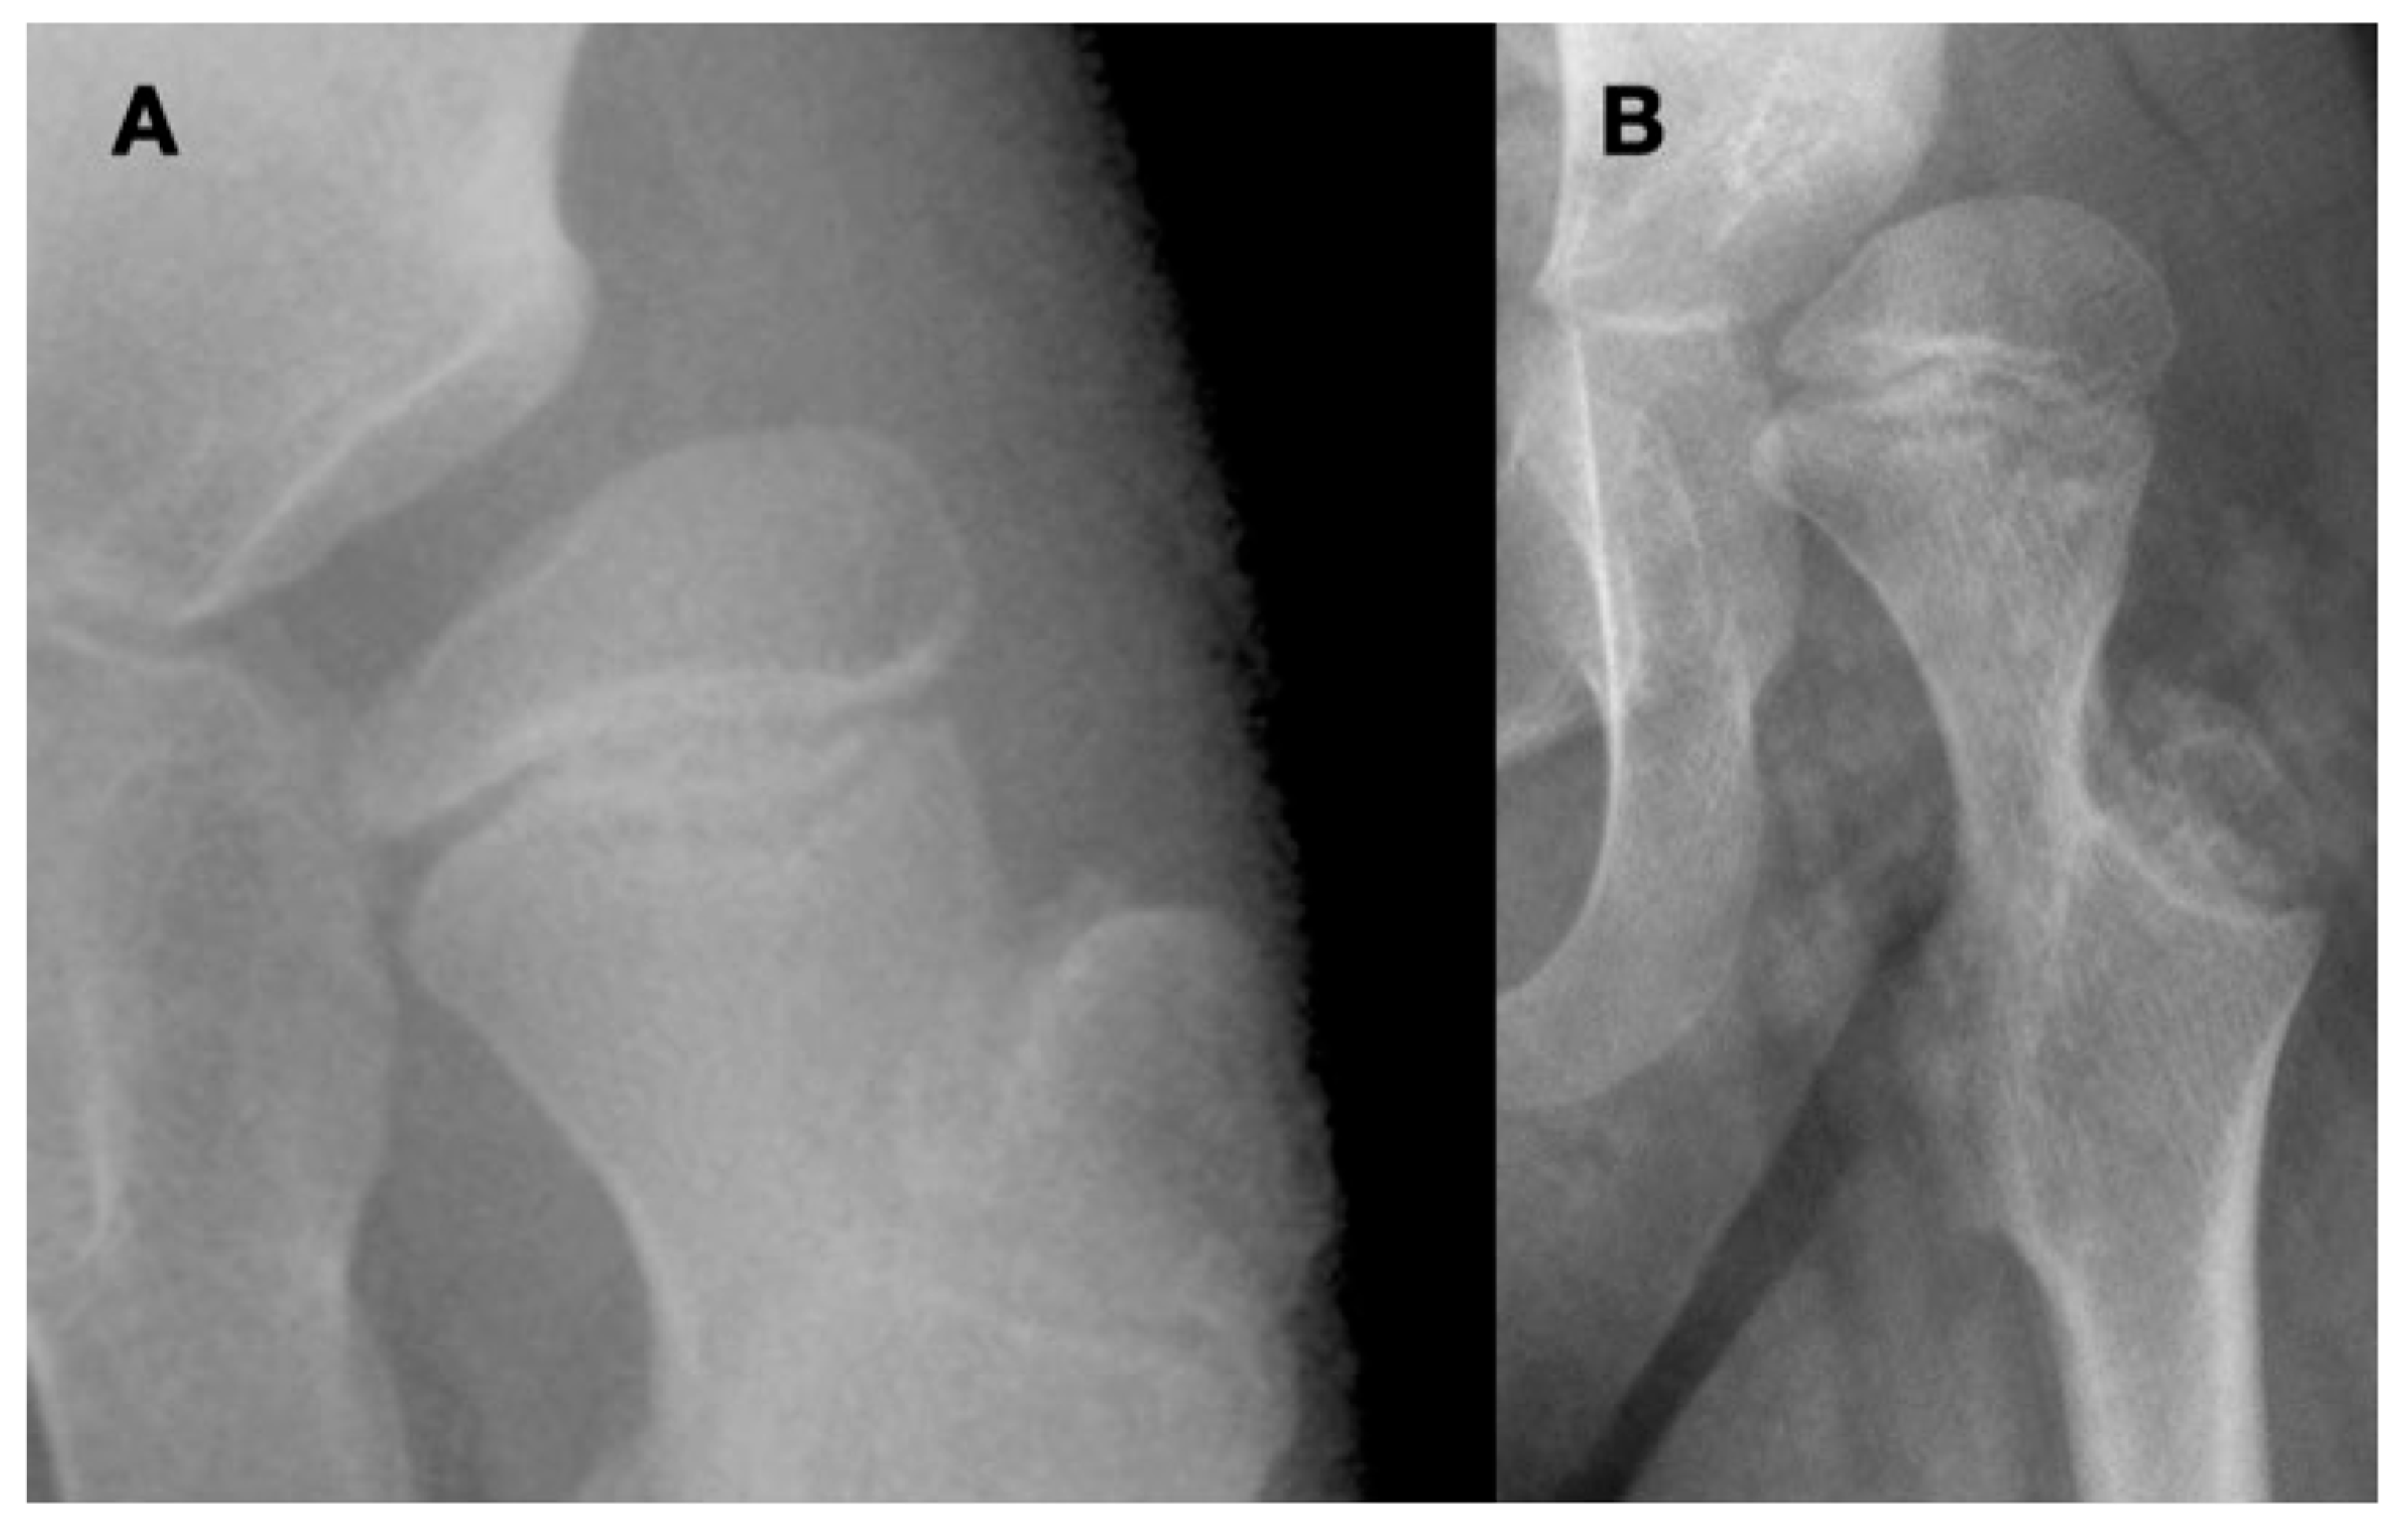

3.4.2. Pathologic Role of Coxa Valga and the Impact of its Correction on Spastic Hips

4.1.2. Pathologic Role of Coxa Valga and the Impact of its Correction in Weak and Hypotonic Hips

4.1.3. Pathologic Role of Coxa Valga and Treatment Options in Paralytic Hips

4.2. New Treatment Options